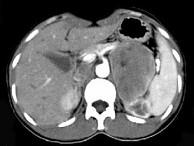

问题 女,36岁,无任何症状,体检时超声发现左侧肾上腺区占位,CT扫描如图所示,应诊断为()

选项 A.左肾上腺腺瘤 B.左肾上腺囊肿 C.左肾上腺嗜铬细胞瘤 D.左肾上腺髓样脂肪瘤 E.左肾上腺转移瘤

答案 A